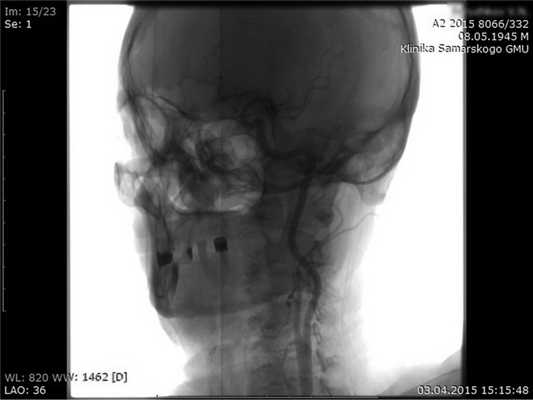

Первым этапом выполнили доступ к бифуркации СА и вертикальной части V3 сегмента ПА в промежутке СI-СII поперечных отростков позвонков. На бедре сделали забор участка большой подкожной вены для шунта. Перед пережатием артерий вводили внутривенно 5000 ЕД нефракционированного гепарина. Выполнили каротидную эндартерэктомию по эверсионной методике (атеросклеротическая бляшка с ровной поверхностью, стеноз до 60%). Затем формировали аутовенозный шунт между V3 сегментом ПА в промежутке поперечных отростков СI-СII позвонков и общей СА ниже ее бифуркации.

Рис. 3. Эверсионная каротидная эндартерэктомия. Формирование аутовенозного шунта V3 сегмента ПА - общая СА.